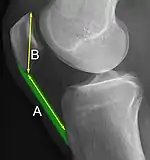

The Insall-Salvati ratio helps to indicate patella baja on lateral X-rays, and is calculated as the patellar tendon length divided by the patellar bone length. An Insall-Salvati ratio of < 0.8 indicates patella baja.[6]

A patella alta is a high-riding (superiorly aligned) patella. An attenuated patella alta is an unusually small patella that develops out of and above the joint.

A patella baja is a low-riding patella. A long-standing patella baja may result in extensor dysfunction.[5]